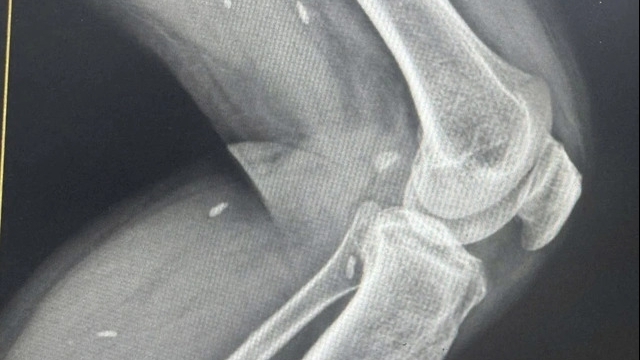

![]() |

| Các bác sĩ thực hiện chia gan để ghép cho 2 bệnh nhân |